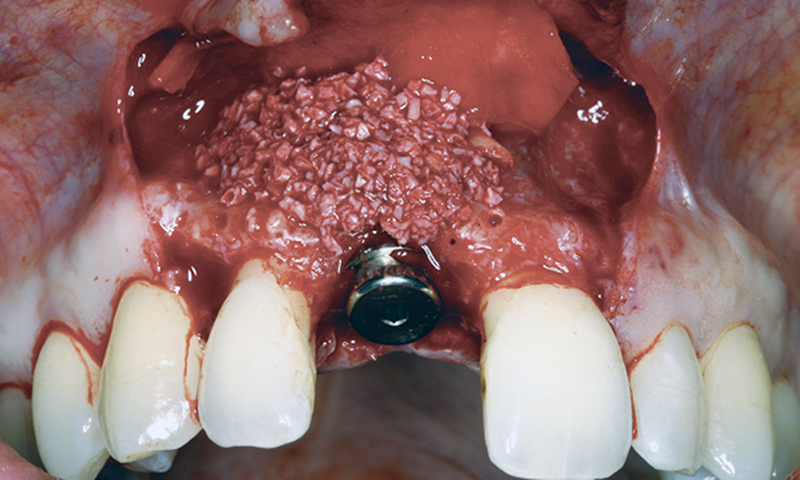

Bərpa texnikasının müəyyən edilməsi, sümüyün hansı bölgədə, hansı miqdarda itirilmiş olmasına bağlı olaraq müəyyənləşdirilir. Bərpa üçün tətbiq edilən sümük materialları pasiyentin öz donor bölgələrindən xüsusi metodlarla qazanılmış sümüklər, o cümlədən digər fərdlərdən alınmış və xüsusi qaydada hazırlanmış materiallar, heyvan mənşəli sümükəvəzləyici materiallar və sintetik materiallar olaraq ayrılır.

Bərpa zamanı yerinə görə bu materiallar ya ayrı-ayrılıqda, ya da kombinə olunmuş şəkildə tətbiq oluna bilir. Gündəlik təcrübədə həmçinin pasiyentdən götürülmüş qan nümunələrindən alınmış yüksək bərpaedici xassəyə malik materiallar (PRF) da uğurla tətbiq olunur. Sümükartırma metodlarının tətbiqi sayəsində, çənədə implantların yerləşdirilməsi üçün yetərsiz sümük həcmi olan bölgələrdə sümük miqdarı yetərli duruma gətirilir, uyğun boy və diametrə uyğun implantlar uğurla tətbiq olunur.